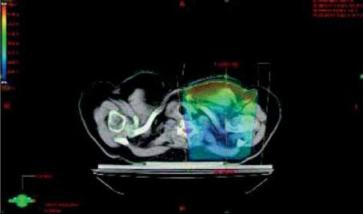

- Při ozařování hrudní stěny s jizvou po totální mastektomii, u

inflamatorního nebo inoperabilní karcinomu je u techniky

tangenciálních polí vhodné použít bolus k dosažení potřebné dávky

na kůži. Bolus na celé pole je doporučován asi na polovinu celkové

ozařovací doby, dále jen na oblast jizvy (Perez C. 1999).

Na ONO Č. Budějovice u pacientek po mastektomii byla měřena dávka TLD na kůži pod bolusem a dávka na bolusu: dávka pod bolusem1,8-2 Gy, na bolusu 1,5-1,6 Gy (obr.5a, b). TLD umožnily zvolit tloušťku bolusu. Na ONO Č. Budějovice se používá bolus na celou plochu tangenciálních polí do 30 Gy, dále je na oblast jizvy a okolí. - Při plánování radioterapie je nutné hodnotit dávku v kritických

Obr. 5 Optimalizace RT tg pole bez bolusu a s bolusem